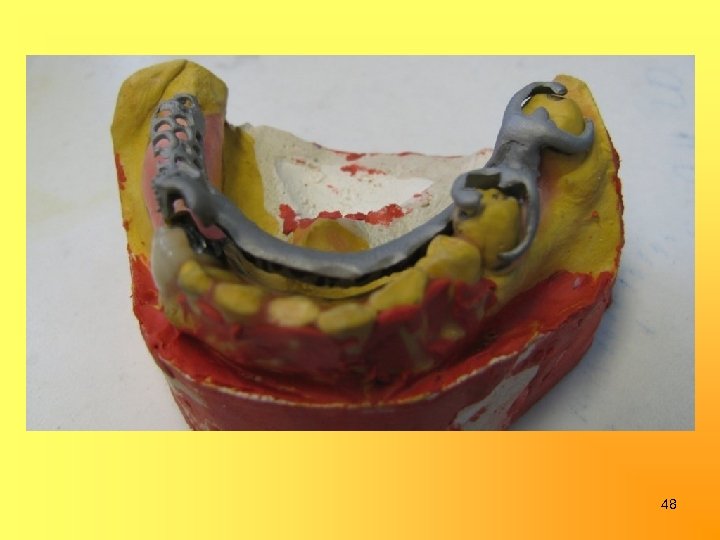

Изготовление бюгельных протезов в/ч и н/ч с замковыми креплениями на 15, 24, 43 и опорно-удерживающими кламмерами на 37 и 35 35

48

Эпикриз. Пациент В. обратился в стоматологическую поликлинику с жалобами на нарушение жевательной функции, эстетики, подвижность зубов. В ходе ортопедического лечения были изготовлены следующие конструкции: штампованная металлическая коронка на 37 зуб, культевые штифтовые вкладки на корни 11, 12 зубов, металлокерамические мостовидные протезы с опорой на 15, 13, 12, 11, 23, 24, 43 зубы и бюгельные протезы в/ч и н/ч с замковыми креплениями на 15, 24, 43 и опорноудерживающими кламмерами на 37 и 35. Жевательная эффективность восстановлена до 100%, эстетика возвращена. 60